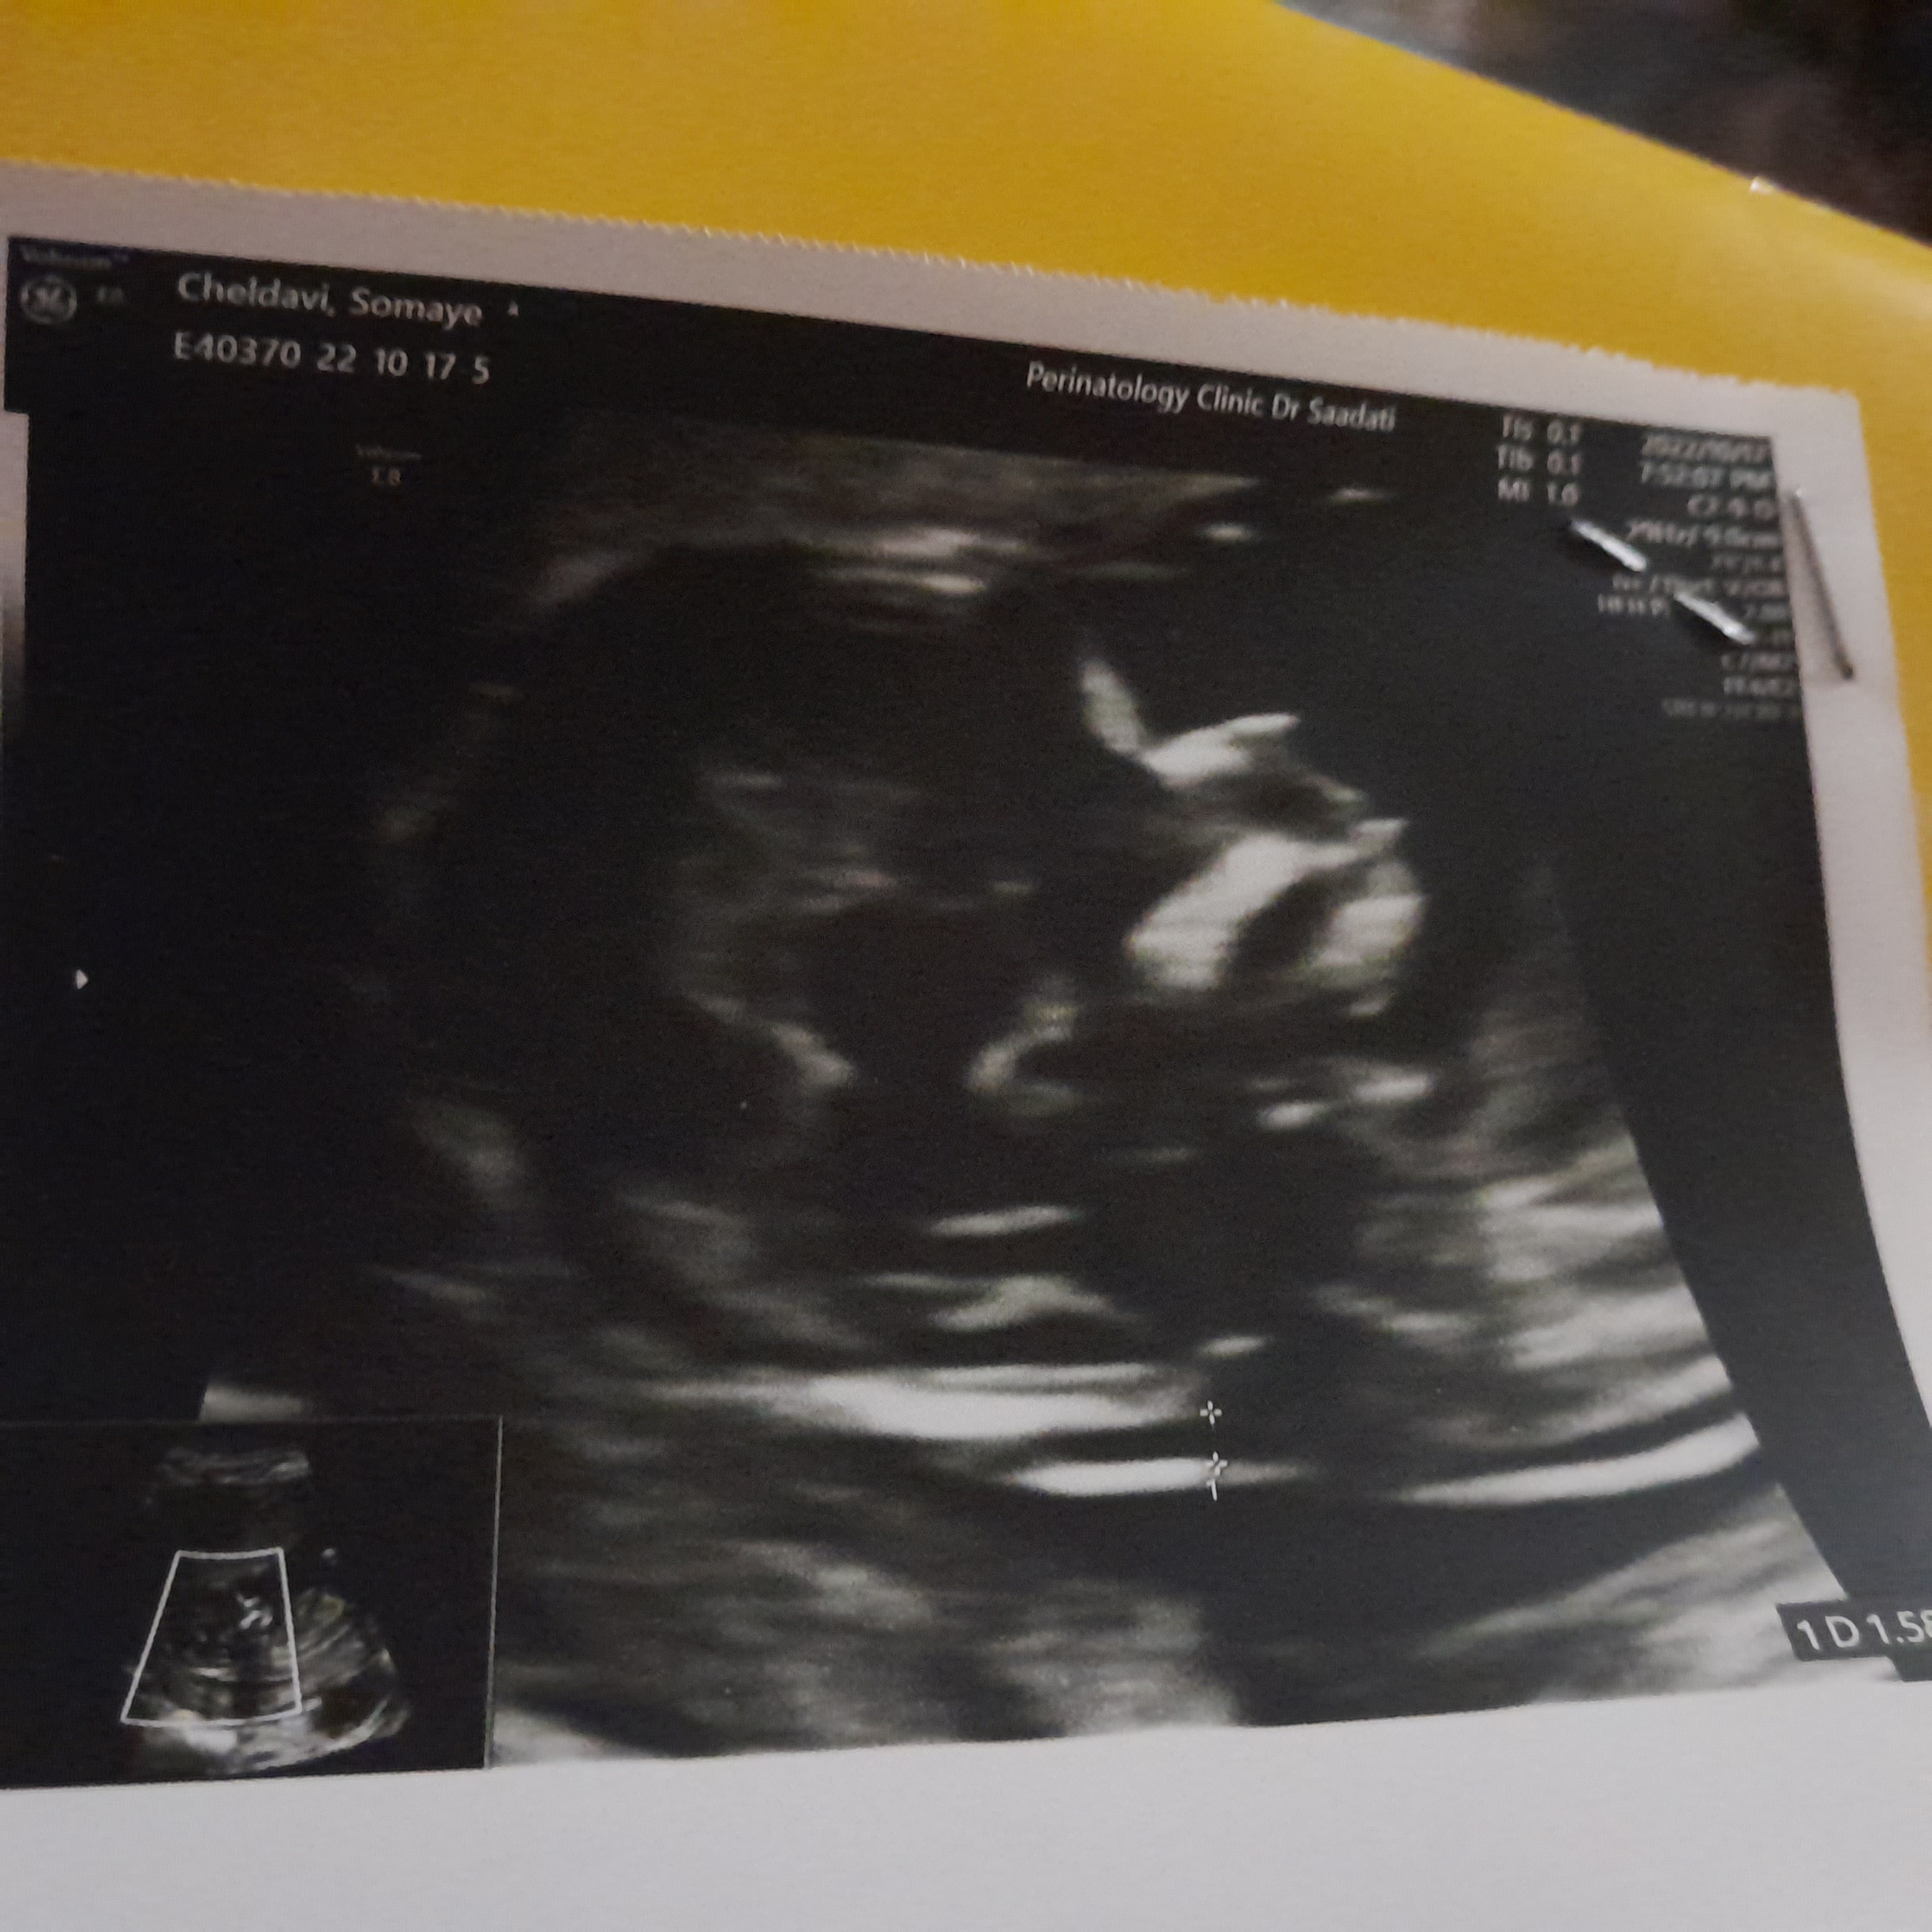

جدی؟ یه سوال همه بچه ها توی ۱۳ هفته این شکلین؟ یا فقط بچه من اینطور خیلی ناراحتم فکر میکنم بینی و پی ...

😂😂ن فقط جمجه پسر اینجوری تو این هفته ها بعد مثل هم میشن واسه دختر پیشونیش صافه منم رفته بودم میگفتم وای چ دماغی داره بچم بعد ک دنیا اومد دماغش اندازه نخود😁